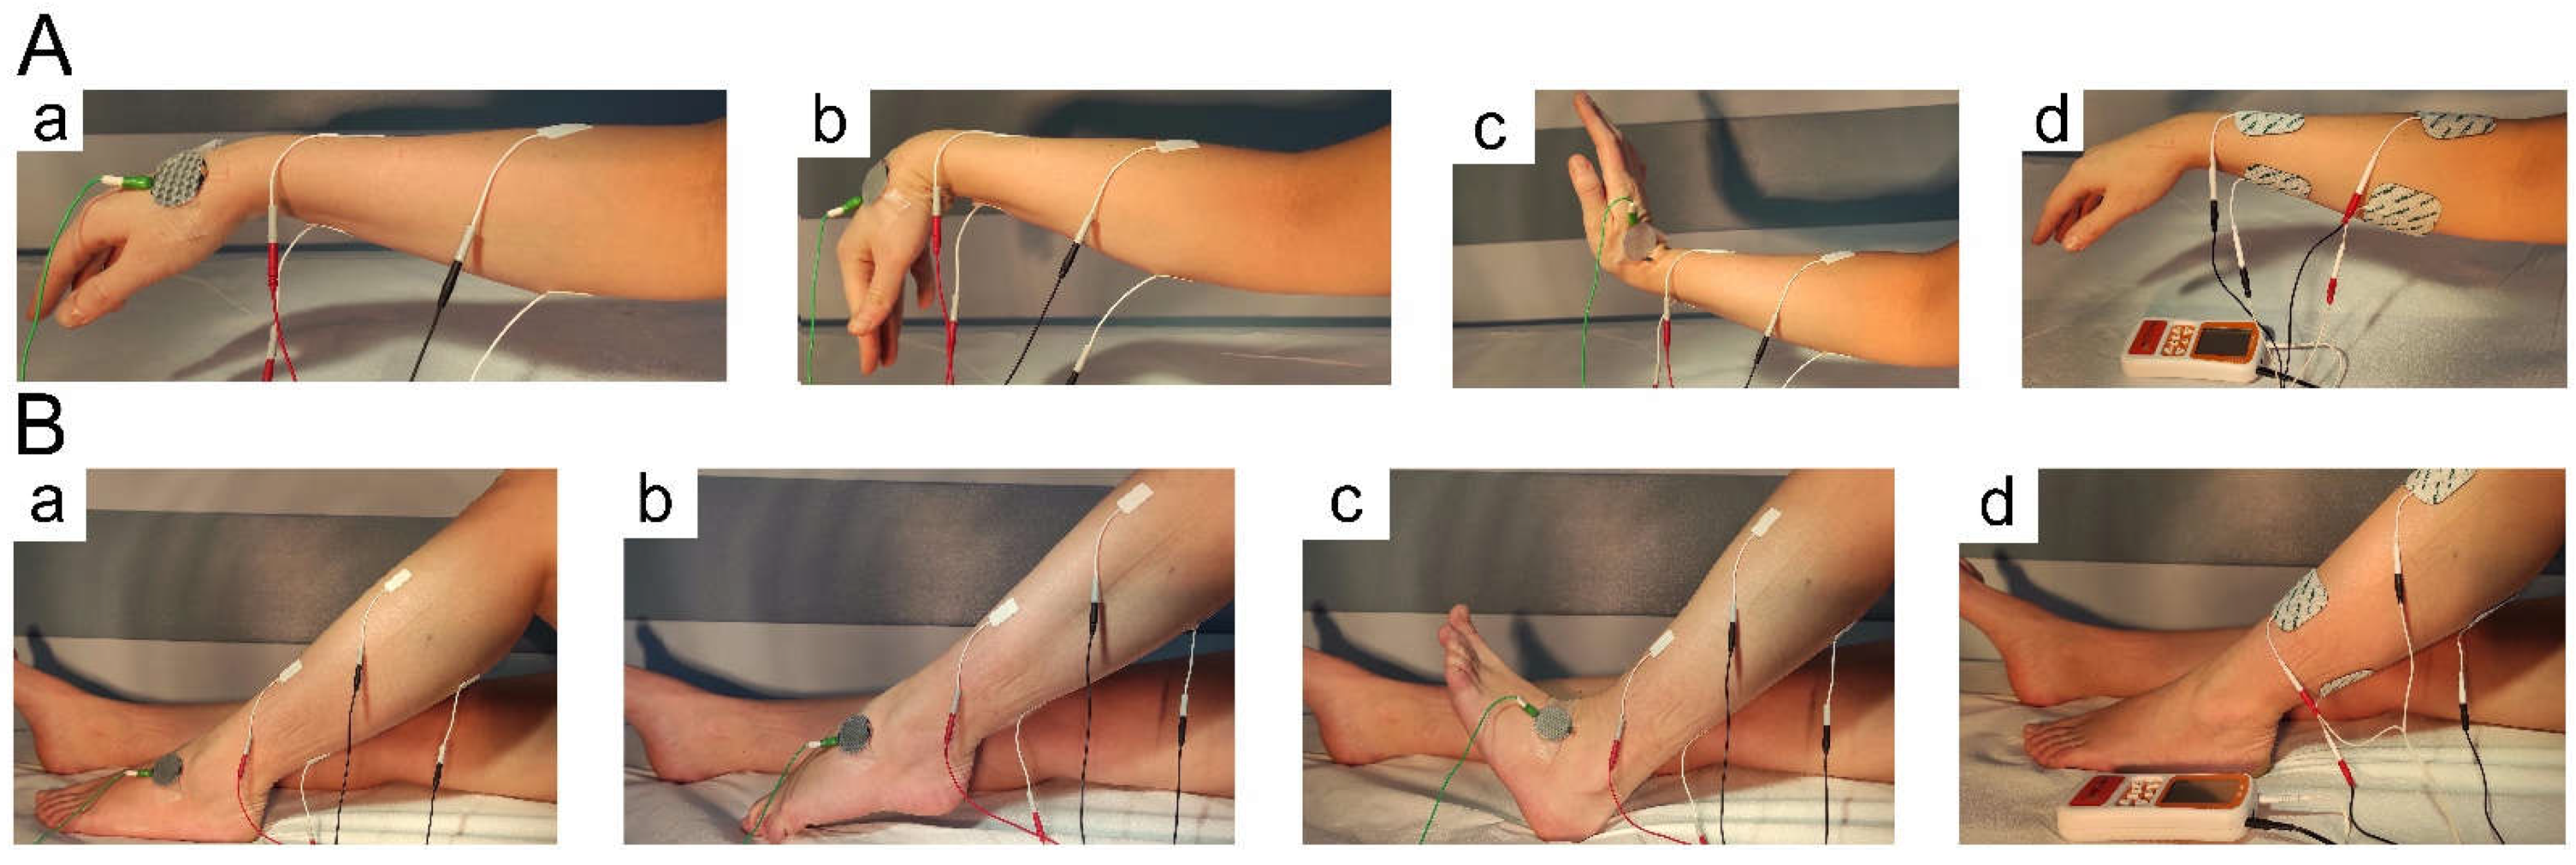

2.3. Treatment with NMFES